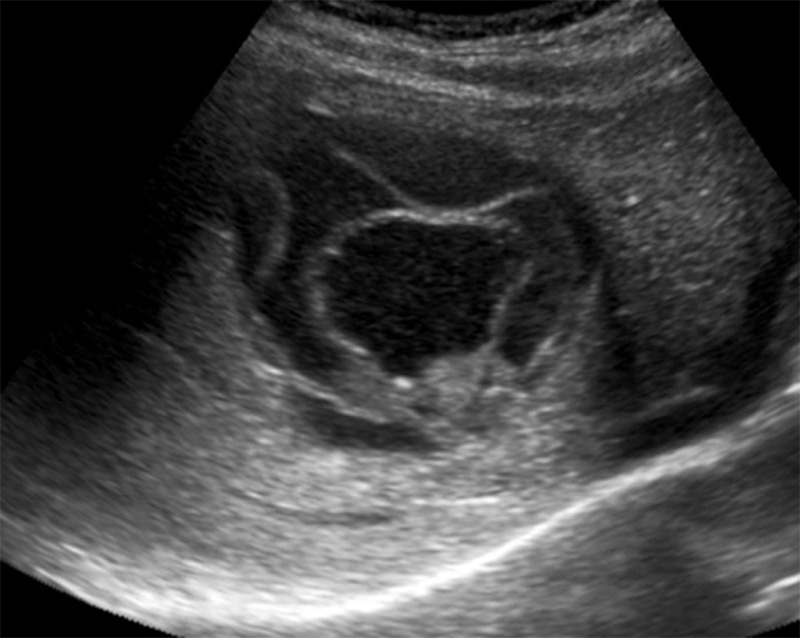

- Most often single, usually in the posterior right lobe.

- Thin or invisible wall, hypoechoic, more uniform texture.

Figure 25. Large right lobar liver amoebic liver abscess. Note the complex heterogeneity and dirty shadowing.

Figure 26. A still image of the same right lobar liver amoebic abscess.

Figure 27. Transverse epigastric view of a separate left liver lobar amoebic abscess in the same patient.